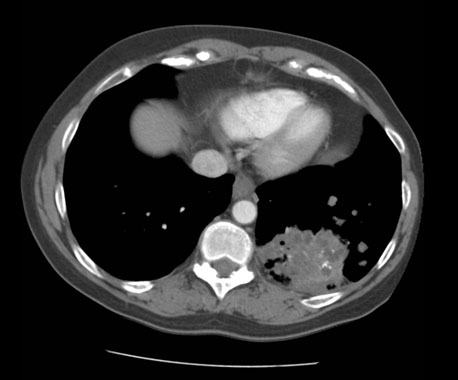

A 51-year-old female with a 50 pack-year smoking history was referred to the hospital after an outpatient chest X-ray, and subsequent computed tomography (CT) of the chest from 14 March 2019 (Figure 1), which reported a large left hilar lung mass. She reported worsening dyspnea and cough for three months, associated with intermittent pleuritic chest pain, reduced appetite but no significant weight loss. She was hypoxic, saturating at 93% on 3 liter on nasal prongs at the time of presentation to hospital with widespread wheeze.

Her past medical history included chronic obstructive pulmonary disease, adrenal adenoma, hypertension, transient ischemic attack, fatty liver, depression, and diverticular disease. She denied history of alcohol use and had no pertinent family history of malignancy. The chest CT revealed a large left hilar mass obstructing the upper as well as lower lobe bronchi with near-total collapse of the upper lobe of the left lung and evidence of obstructive patchy pneumonia in the residual upper and lower lobes of the left lung. Abdominal CT also noted abdominal lymphadenopathy with possible adrenal metastasis.

Figure 1: Baseline CT chest (14 March 2019) showing left lung mass on diagnosis.